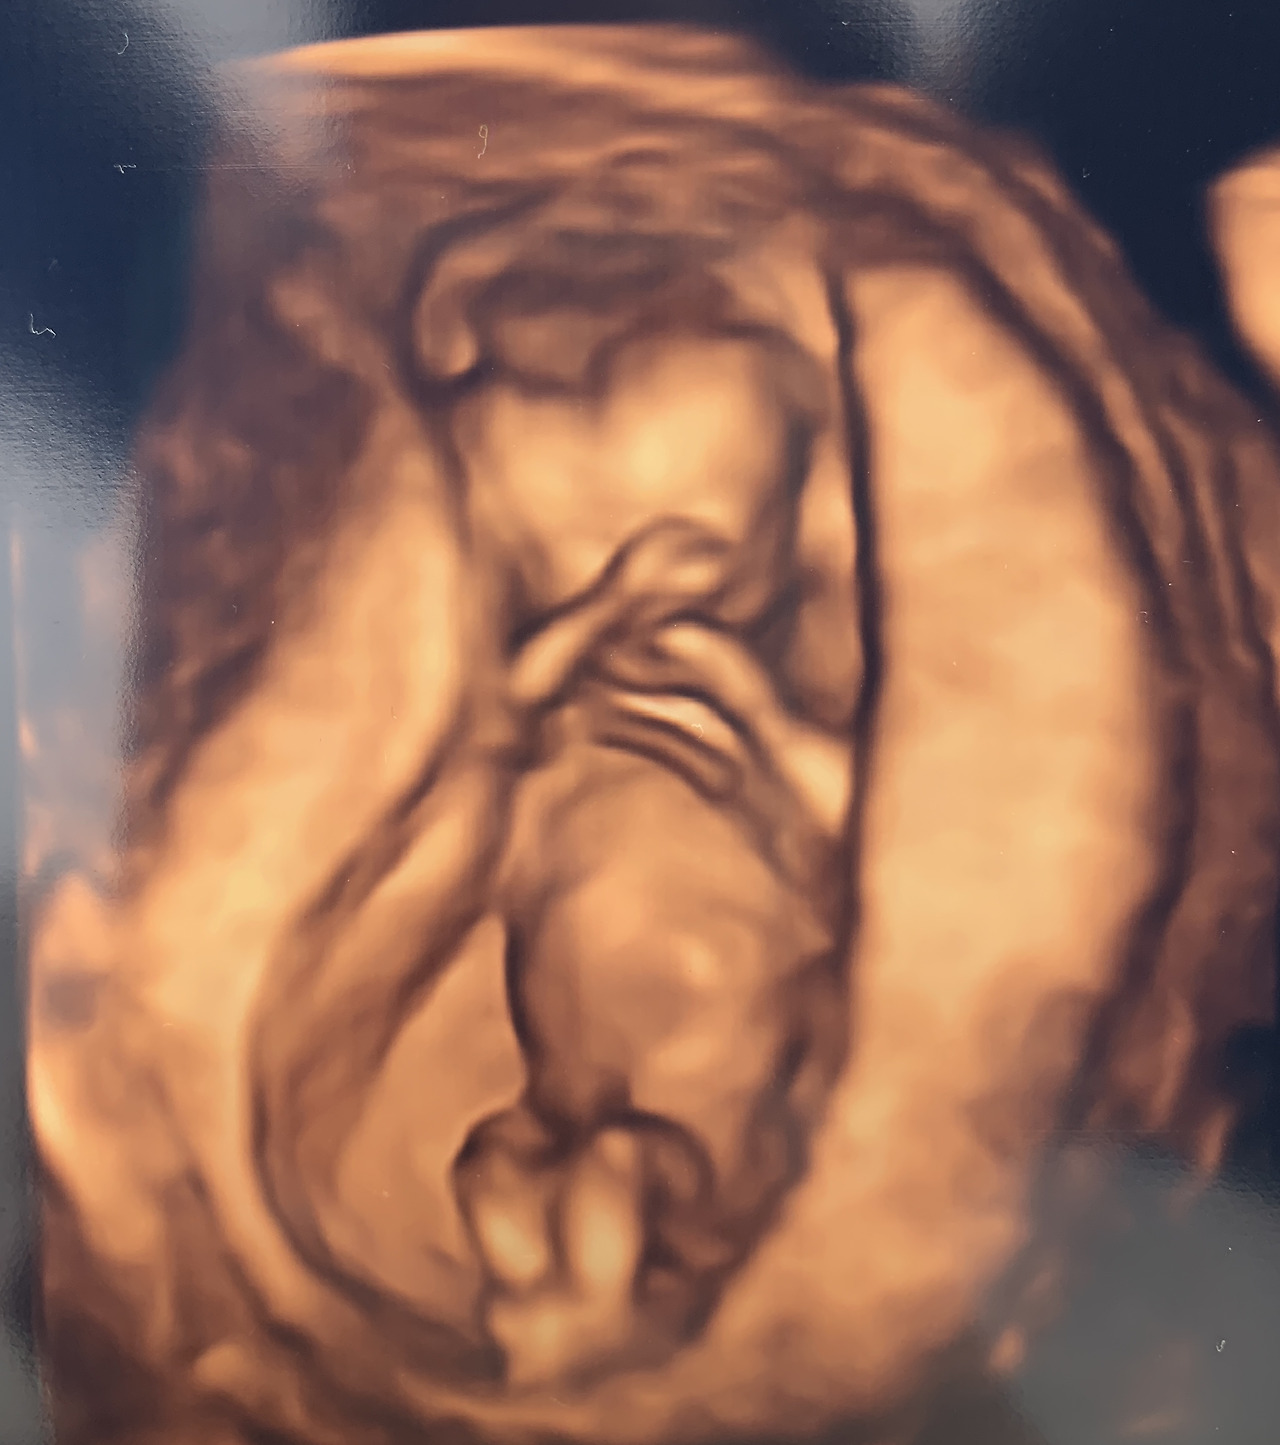

이리저리 초음파가 예쁨이를 비췄다. 심장도 참 잘 뛰고 있었다. 초음파 선생님은 마우스 포인터로 목의 두께와 예쁨이의 키 등을 굉장히 능숙하게 측정했다. 초음파만 하시는 분이라 그런지 기계가 아내의 배를 여기저기 시원하게 가로지르며 할 일을 했다. 그때 예쁨이는 꼬물꼬물 움직이다가 팔과 다리를 꼬았다. 나 쉬운 태아 아니다 라고 어필하는 것 같았다. 그리고 곧 말로만 들어본 입체 초음파를 볼 수 있었다. 그림자처럼 보던 일반 초음파와는 다르게 원근감과 질감까지 느껴지는 듯한 입체 초음파는 신세계였다. 처음 나왔던 휴대폰의 단음 벨소리를 듣다가 16화음 오케스트라 휴대폰 벨소리를 들었을 때의 업그레이드 감이라고 하면 얼마나 많이들 이해하실까? 역시 휴대폰은 잘 걸리는 걸리버. 중요할 땐 꺼두셔도 좋습니다 스피드 011. 요금제는 나눠 쓰는 비기 알 요금제. 여하튼 아직 이목구비나 성별을 구별할 만큼 뚜렷하진 않지만 입체 초음파는 확실히 머리와 몸, 팔과 다리, 탯줄과 예쁨이의 움직임이 더 섬세하게 담겼다.

img.jpg

12주 입체 초음파 사진이다. 아름답게 빚어지고 있다. 황홀한 초음파를 마친 후 상담실에 가서 간단한 문진을 했다. 병력이나 수술력 등을 확인하고 산전검사의 항목을 체크했다. 예를 들면 풍진이나 A형 간염, B형 간염, 수두 등이었다. 오늘 또 한 번의 채혈을 통해 다시 필요한 항체들을 확인할 거라고 한 것 같다.

상담실에서 나와 이제 담당 의사 선생님을 만났다. 드디어 오늘 1차 기형아 검사의 결과를 들을 시간이다. 촬영된 초음파를 이리저리 보시며 매우 확실한 어조로 이야기를 하시기 시작했다. 가장 긴장되는 순간이었다. 일단 오늘 검사 결과로는 목 두께의 수치 정상, 태아의 크기도 정상, 코 뼈도 잘 자랐고 뇌의 발달도 잘 되고 있단다. 탯줄도 잘 있고 손 발도 잘 발달하고 있다고.. 부족했던 양수도 이제 적당하다고..(물 먹느라 고생했어 여보. 쉬 싸느라 고생했어 여보) 요즘 나에게 있어서 최고의 순간은 아내가 건강하다는 소리와 아기가 잘 있다는 소리를 들을 때이다. 하나님 감사합니다. 그리고 또 한 가지 정말 기뻤던 것은 의사 선생님의 입에서 ‘안정기’라는 단어가 나왔다. 전에 썼듯이 임신에 있어서 안정기란 없지만 그래도 아주 조금은 안심할 수 있는 단계에 오면 ‘안정기’라는 단어를 쓰나 보다. 의사 선생님께서 안정기에 들어섰으니 무리하지 않는 선에서 조금씩 활동해도 좋다고 말씀하신다.(산책은 30분부터 조금씩 늘려가는 게 좋다고 한다) 선생님의 ‘안정기’ 거론은 마치 마법의 주문처럼 우리 마음을 안정시켰다. 반가운 말은 백번 천 번 들어도 좋다. 이 반가운 말 몇 번 더 들으면 곧 산달이 되겠다.